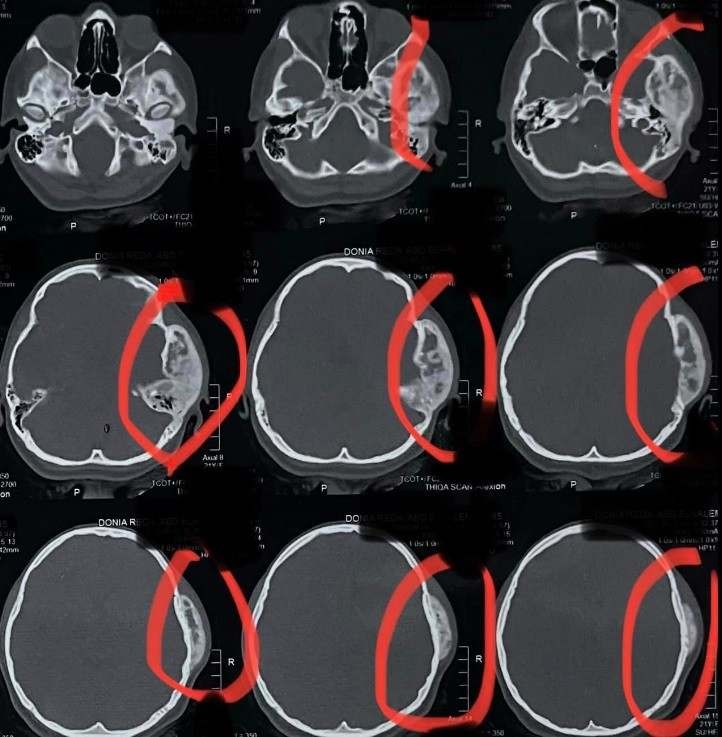

A 21-year-old female suffering from bone fibrous dysplasia was diagnosed and treated. This disease is characterized by the growth of benign bone tumors in multiple body areas, which can affect motor function and cause chronic pain.

• Accurate diagnosis using advanced imaging

• Periodic imaging follow-up